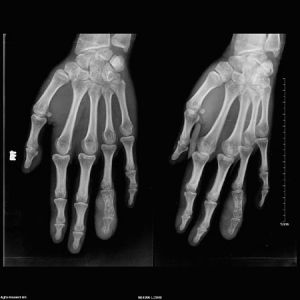

X片效果診斷依據

3.X線拍片顯示:患指骨質有破壞等。